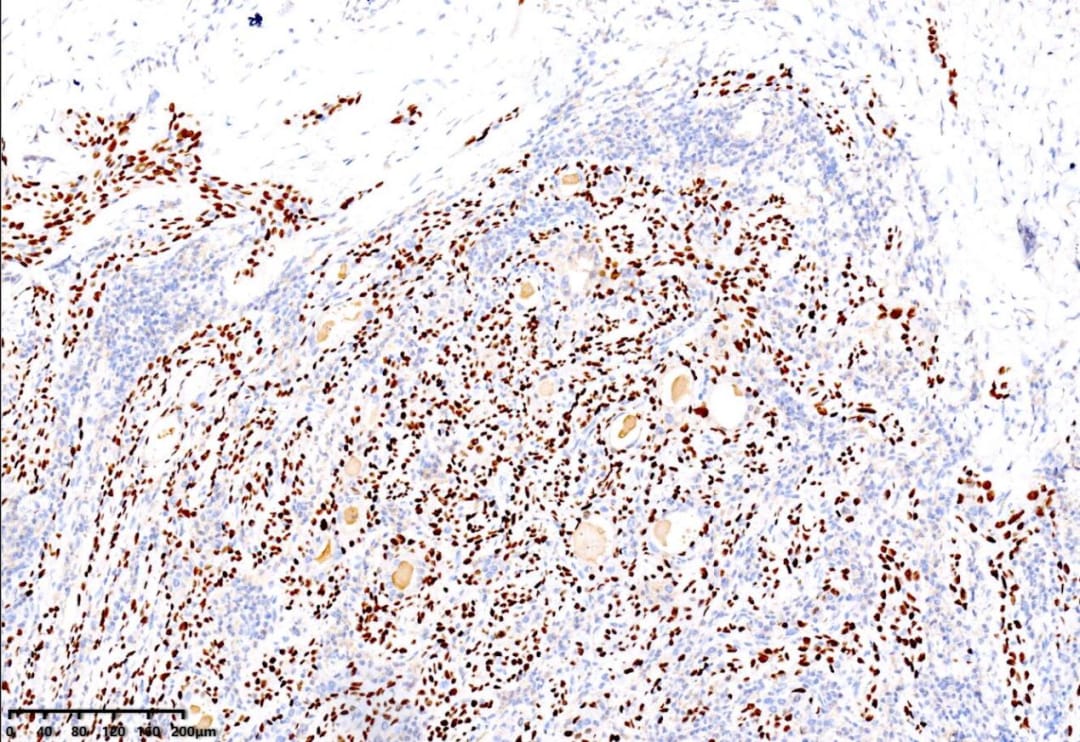

低倍镜,右侧为甲状腺组织伴淋巴细胞浸润,左侧为纤维间质内见肿瘤组织浸润性生长

免疫组化结果显示:CK19(+)、p40(+)、p63(+)、PAX8(+)、TTF-1(+)、CK5/6(+)、CyclinD1(+)。值得注意的是,BRAF V600E(部分+)和p53突变型阳性,Ki67阳性指数约15%。这些分子标记物对于确诊和鉴别诊断至关重要。

P63(+)

PAX8(+)

TTF-1(+)

CyclinD1(+)